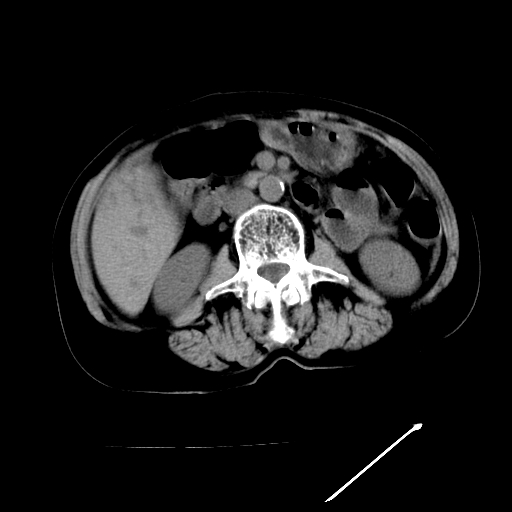

以下是引用随光逐影在2009-4-7 8:21:00的发言:[br]肝内外胆管多发性结石并肝内外胆管扩张;胆系感染。